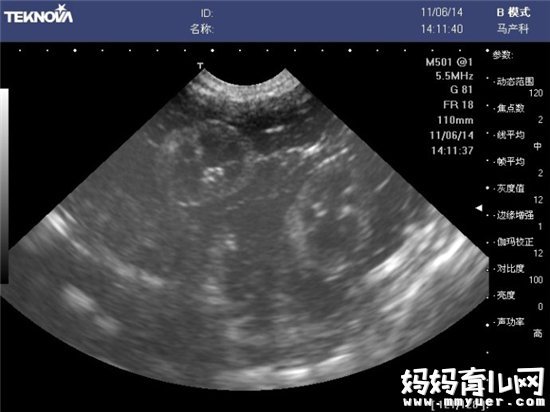

目前临床上所应用的B超,其探头发射的声强度小于10mW/cm,而且超声检查的时间往往只有5-10分钟,对每个器官的探测时间更短。所以说,B超检查对胎儿的危害极小,不会影响其身体发育。因此,孕妇不必对孕期B超检查产生恐惧心理,适时的B超检查是确保胎儿正常发育的重要手段。

在整个怀孕期间,早、中、晚期应各进行一次B超检查。有些孕妈对做B超的目的不明确,为了弄清楚胎儿性别,不惜到多家医院反复进行B超检查,这对母婴均不利。有研究证明,如果照B超的时间超过了20分钟,就会对胎儿产生不可逆的不利影响。所以,建议孕妇整个孕期如果没有出现异常状况的话,不要随便做B超。